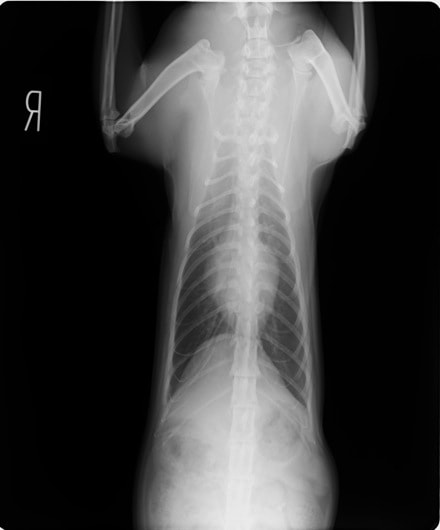

症例1:【マルチーズ 12歳齢 去勢オス】

A:胸部レントゲン写真 正面像

胸部レントゲン検査において重度の心拡大と肺水腫が認められた。超音波検査では、重度の僧帽弁閉鎖不全症、三尖弁閉鎖不全症、中程度の大動脈弁閉鎖不全症を合併していることが判明した。三尖弁逆流速度から肺高血圧症が示唆された。